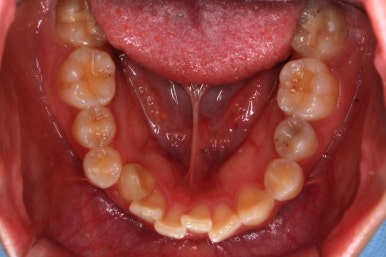

위 사진은 연산동교정치과 처음 내원하셨을 때의 입안 모습입니다. 몇 가지 모습이 관찰됩니다.

치아가 삐뚤삐뚤합니다.

위~아래 앞니가 많이 겹쳐서 아랫니가 많이 모이지 않는 "과개교합" 입니다.

앞니가 앞으로 뻐뜨러져 있습니다.